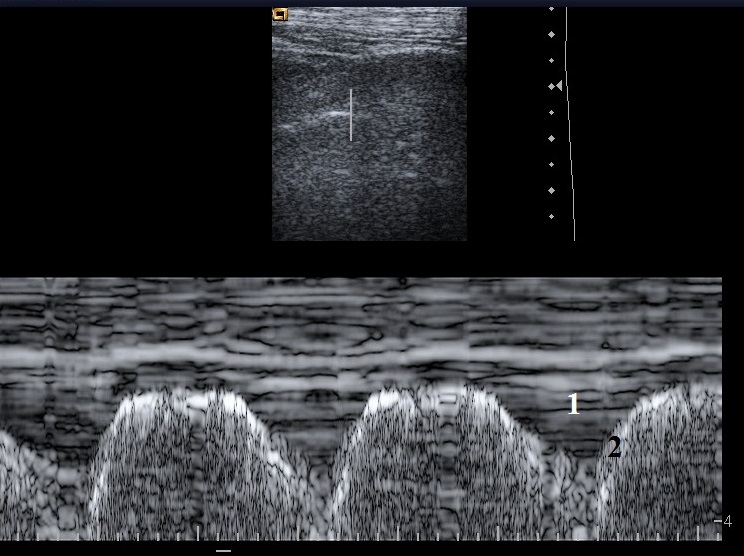

Enregistrement en mode TM (Time Mouvement) d’un autre épanchement pleural minime. Notez, là encore, la cinétique respiratoire de l’épanchement.

1 : épanchement pleural

2 : surface pulmonaire